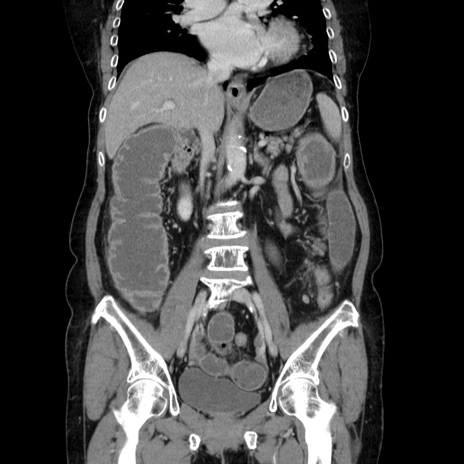

症例5(冠状断像)

【症例】70歳代女性

【主訴】お腹が張る

【現病歴】1週間くらい前から腹部膨満の自覚あり。昨日夜から増悪したため、本日救急外来受診。

【身体所見】意識清明、BT 36.5℃、BP 165/106mmHg、HR 80bpm、SpO2 98%、腹部:膨満、軟、自発痛・圧痛なし、触診にて不快感あり、腸蠕動音:減弱

【データ】WBC 12600、CRP 1.04